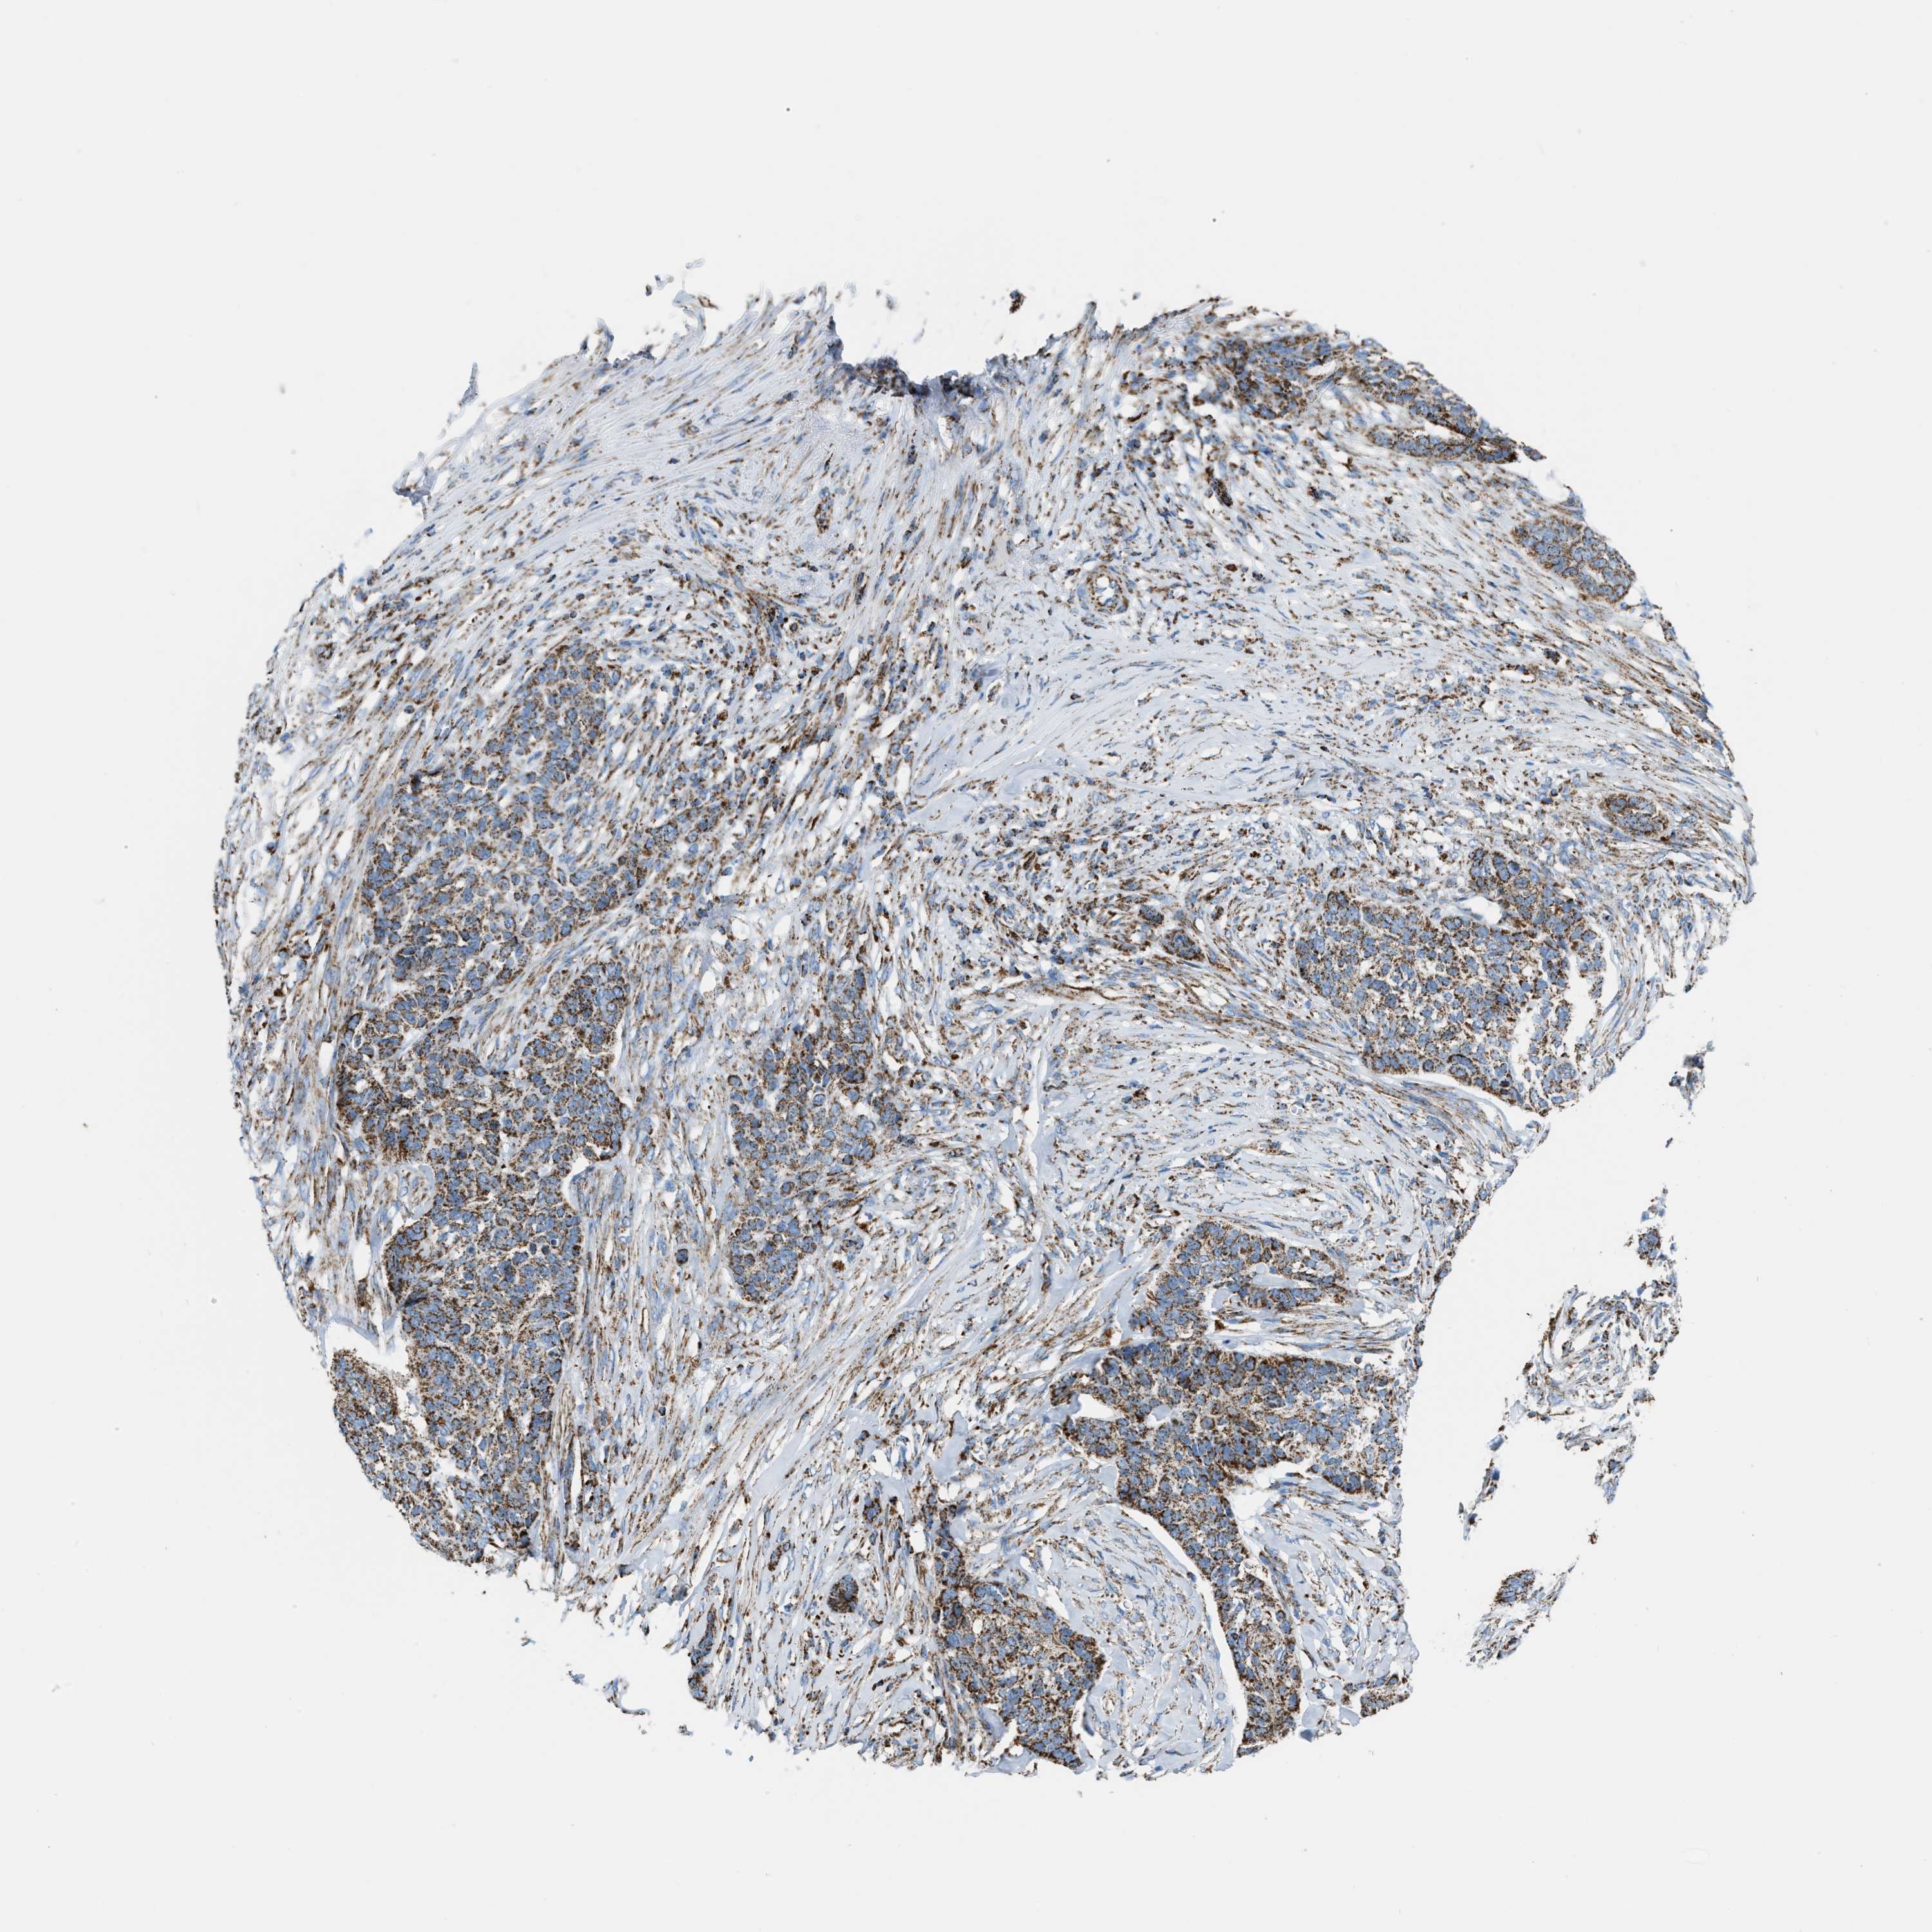

SKIN CANCER - Protein expressioni

A mouse-over function shows sample information and annotation data. Click on an image to view it in a full screen mode. Samples can be filtered based on level of antibody staining by selecting one or several of the following categories: high, medium, low and not detected. The assay and annotation is described here.

Antibody stainingi

Antibody staining in the annotated cell types in the current human tissue is reported as not detected, low, medium, or high, based on conventional immunohistochemistry profiling in selected tissues. This score is based on the combination of the staining intensity and fraction of stained cells.

Each image is clickable and will lead to virtual microscopy that enables deeper exploration of all samples and also displays staining intensity scores, fraction scores and subcellular localization as well as patient and tissue information for each sample.

Antibody HPA018910

Antibody HPA018921

Antibody HPA018923

Staining

High

Medium

Low

Not detected

Intensity

Strong

Moderate

Weak

Negative

Quantity

>75%

75%-25%

<25%

None

Location

Nuclear

Cytoplasmic/membranous

Cytoplasmic/membranous,nuclear

Basal cell carcinoma

Squamous cell carcinoma, NOS

Squamous cell carcinoma, metastatic, NOS